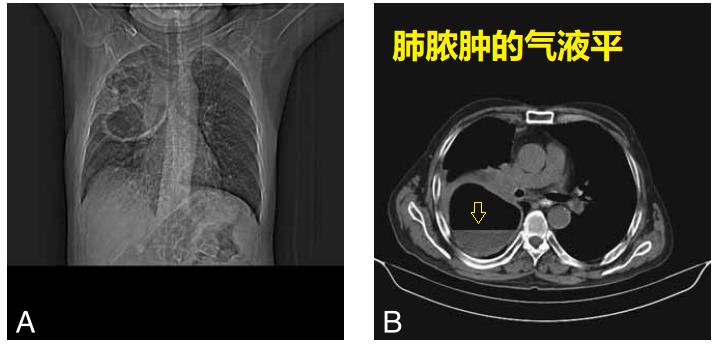

老年男性,抗生素治疗失败。CT示右下叶一大个脓腔。

图07

脓肿穿刺,放置引流管,3周后完全愈合。

图08

26岁女性,肺脓肿,抗生素治疗1周,仍然发热。

CT引导下,肺脓肿穿刺引流(下图B、C),术后随访,脓液完全引出(下图D)。

图09